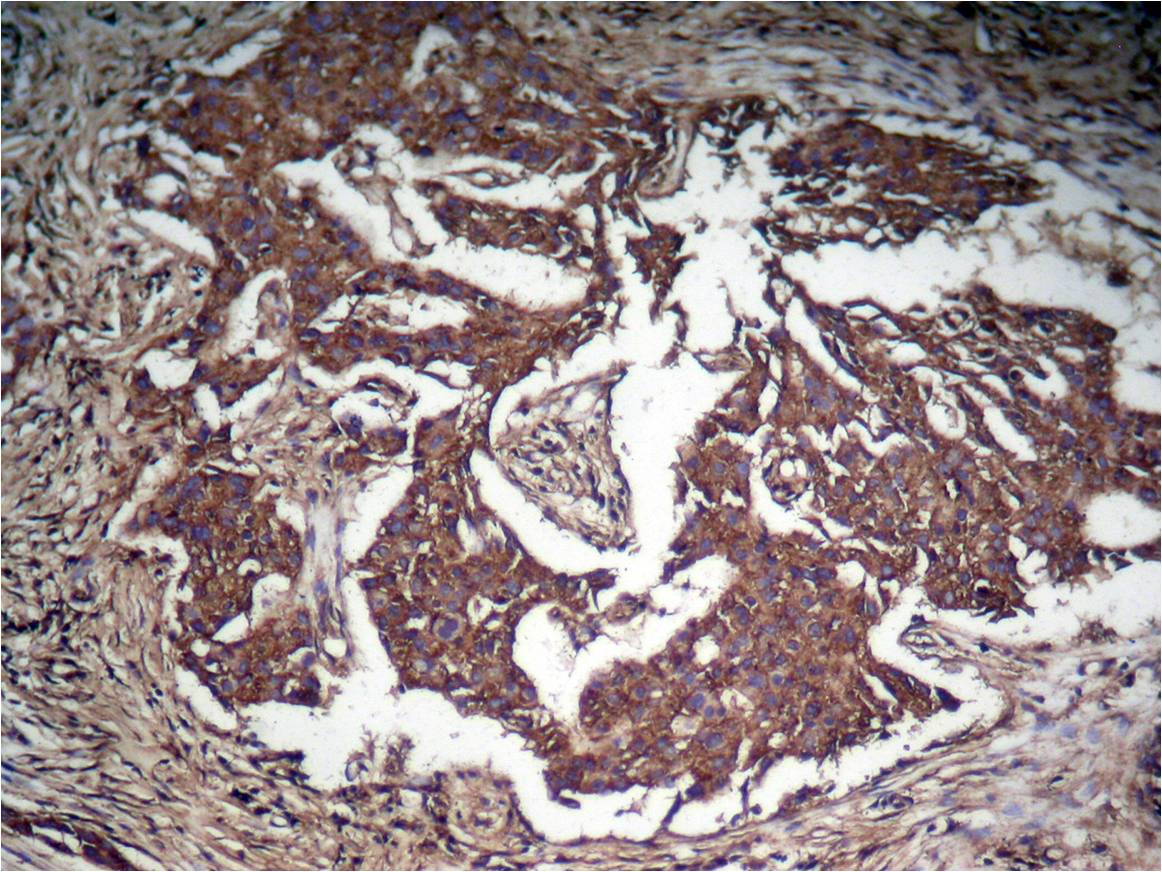

Immunohistochemical analysis of paraffin-embedded human Lung carcinoma tissue using STAT3 (Phospho-Tyr705) Antibody #11045.